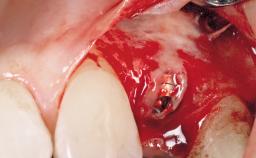

Surgical treatment of a 67-year-old male patient exhibiting an extended edentulous space in the anterior maxilla after the removal of three hopeless incisor teeth.

The video demonstrates implant placement using a surgical stent according to the principle of prosthodontically driven implant placement. The deficient ridge is augmented with locally harvested autologous bone chips, a superficial layer of xenogenic DBBM particles and a resorbable collagen membrane. The surgery is completed with a precise, tension-free primary wound closure.

The case concludes with the presentation of the final prosthesis and the esthetic outcome, demonstrating stable soft tissue conditions and stable bone crest levels at the 3-year follow-up.